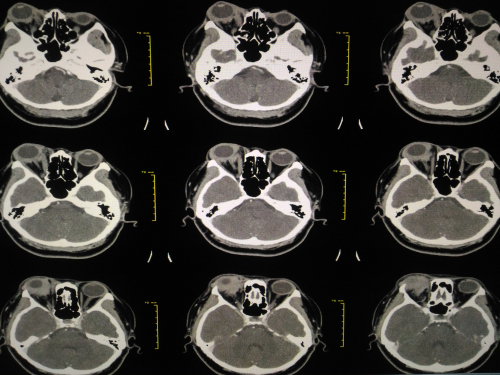

Primary splenic FL is rare, and its clinical and pathological characteristics have not been established. All patients with primary splenic FL underwent splenectomy. In addition, all cases were reviewed by hematopathologists, diagnosed according to the World Health Organization classification (WHO), and had CT imaging.

In the control patients, nodal FL with splenic infiltration was defined as the presence of general lymphadenopathy (enlargement of a lymph node to at least 1.5 cm) and splenic lesions. Cases of splenic lymphoma were identified to not show lymphadenopathy on CT.

Second- or third-generation immunoassay kits were used to test for hepatitis C virus (HCV) status. A splenic lesion was considered present if nodular lesions > 3 cm in size were present on CT. Splenomegaly was defined as enlargement of the spleen to a major diameter of ≥ 12 cm on CT.